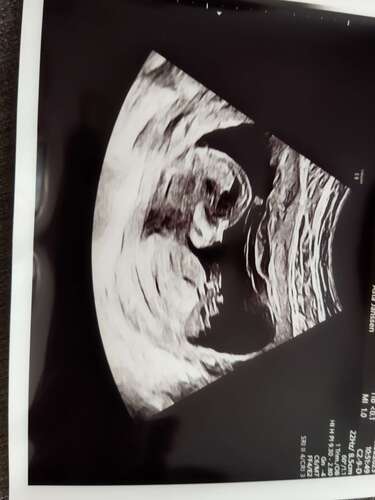

Iemand enige idee? Heel erg bedankt alvast 🥰